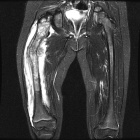

Patient is a 6 y/o female who presented w/ R. thigh pain and inability to bear wt. after attempting to stand for seated position

She c/o R. knee pain for several months w/ fevers and increased inflammatory markers w/ presumed dx. of JRA; PMH: unremarkable

PE: R. thigh swollen/warm with TTP; NVI